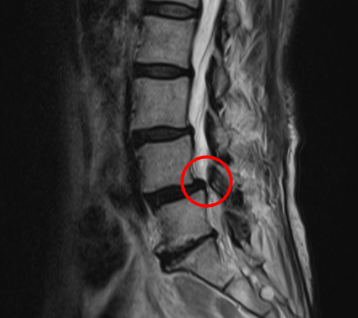

治療前

腰痛MRIを確認したところ、L3/4と、L4/5の2か所に腰椎すべり症が原因とみられる脊柱管狭窄症を認めました。L4/5は特に狭窄が酷くなっていました。

痛みの原因は2か所の狭窄だと考えられます。